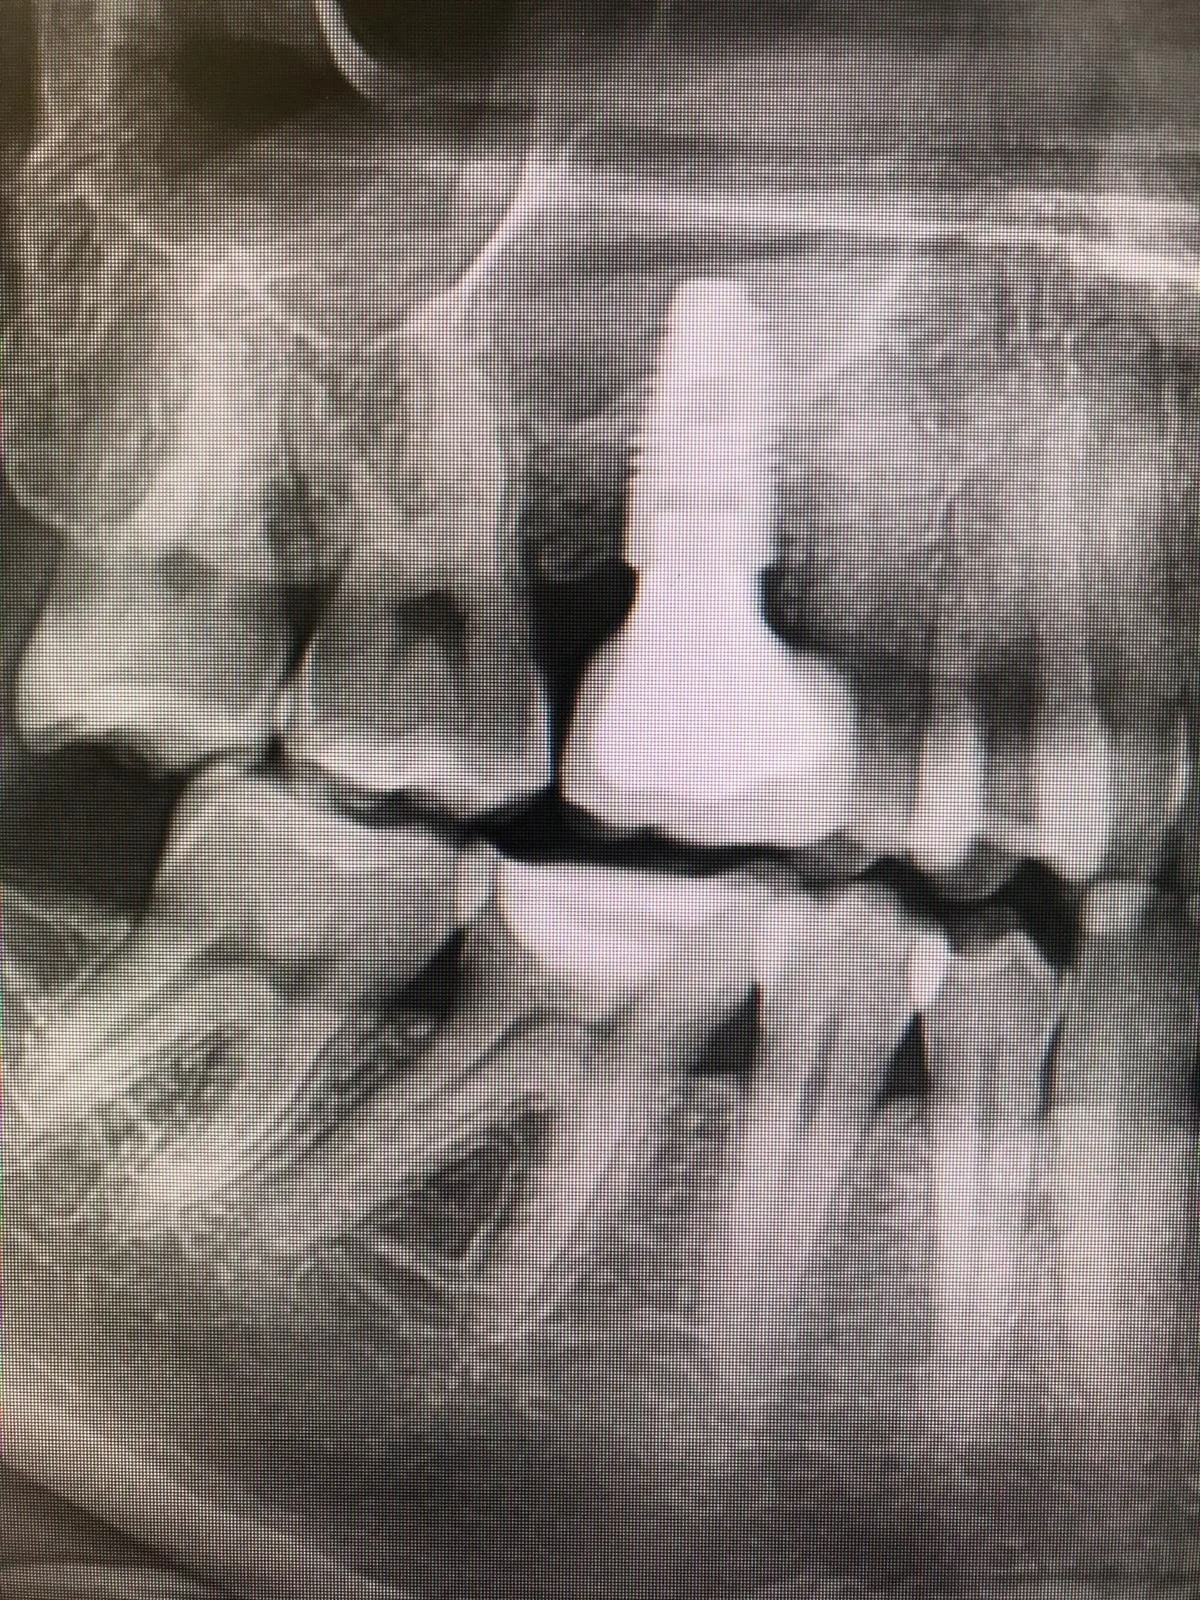

Riabilitazione post estrazione con impianto

Estrazione e Implantologia a Carico Immediato

Estrazione, Rigenerazione Ossea e Riabilitazione Implantare